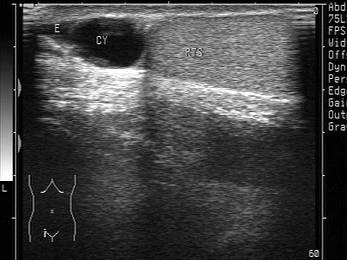

问题 超声于左侧附睾头可探及圆形的无回声暗区,边清。如图所示,考虑为?(?)

选项 A.附睾头囊肿 B.附睾附件 C.睾丸囊肿 D.附睾尾囊肿 E.精索鞘膜积液

答案 A